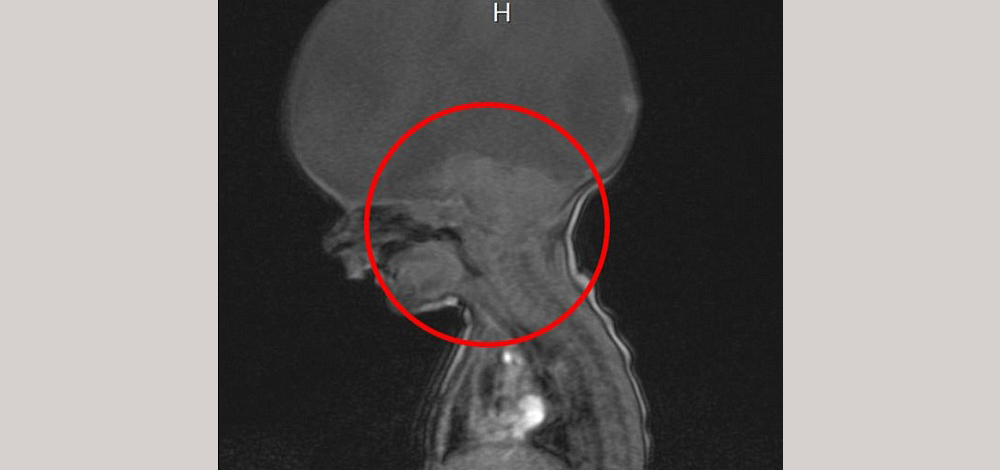

وشخص الأطباء مرض "آرون" بأنه اضطراب نادر يدعى "اندماج مقدم الدماغ"، إذ ولد مع جذع الدماغ فقط، وهو ما يسمح له بالحركة والتنفس، ولكن ليس لديه دماغ كامل .